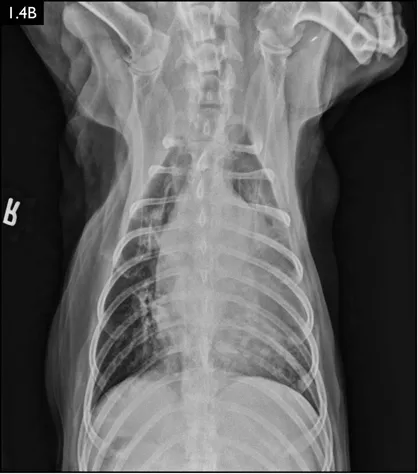

Diagnosis

Clinical signs can be strongly suggestive of bacterial pneumonia, but radiographs are important for confirmation, to characterize the disease (and potential etiology) and to provide a baseline for monitoring response to treatment (Figs. 1.4–1.6). A lag between clinical signs and radiographic changes can occur, and initial radiographs may be normal or appear discordant with clinical severity.

Fig. 1.4A–D Lateral and ventrodorsal radiographs of a dog with doxycycline-responsive pneumonia of unknown etiology before treatment ( A, B) and six days later ( C, D). Note the severe multilobar alveolar pattern that was present initially, most prominently in the left cranial lung lobe. (Courtesy of Atlantic Veterinary College)